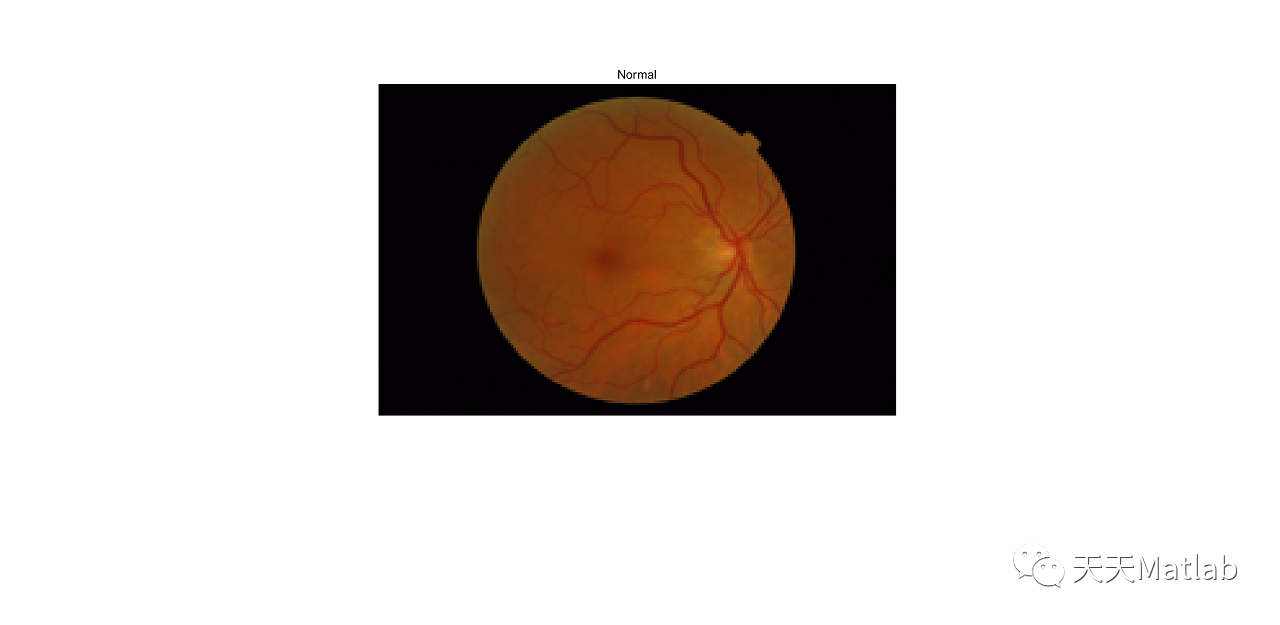

【图像检测】基于CNN深度学习实现图像视网膜病变检测附matlab代码